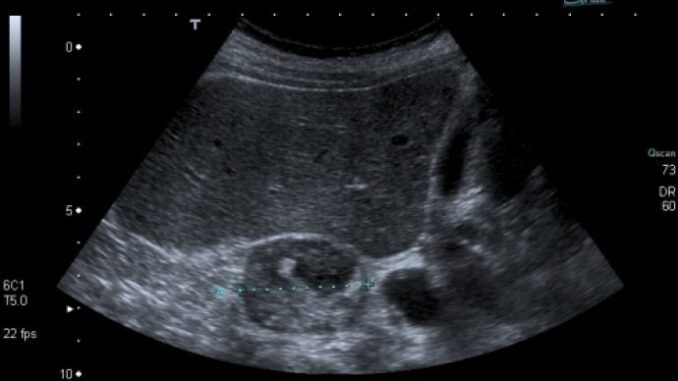

Konačno, tumor nadbubrežne žlijezde može izazvati i pojačano lučenje adrenalina što vodi u visok krvni pritisak, slabost i grčeve u mišićima. Nekada se adenom otkrije tek kada počne da pritiska okolne organe. Tada se dijagnoza može postaviti jedino ultrazvukom nadbubrežne žlezde u lekarskoj ordinaciji.